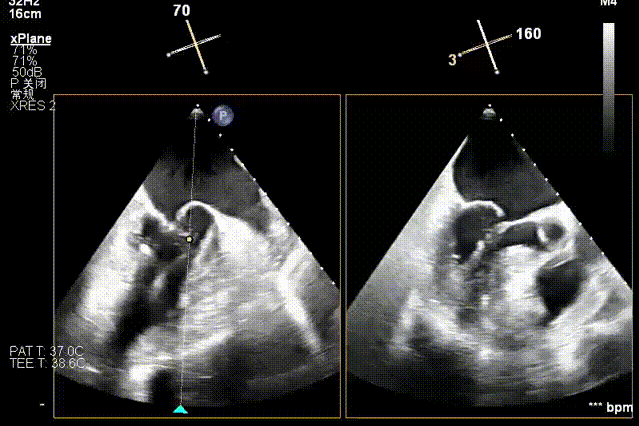

术前经食道超声显示:二尖瓣C1、P1区脱垂,重度关闭不全,彩色多普勒提示大量二尖瓣反流。术前瓣口面积MVA约5cm²,瓣环前后径AP约36.9mm,前叶A1约26mm,后叶P1约15.2mm。